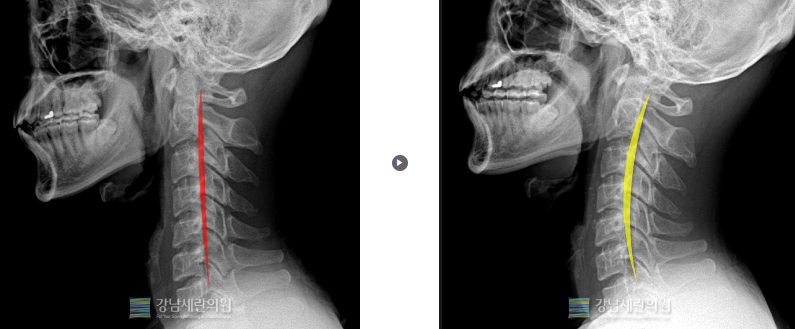

일자목 교정 전 ▶ 일자목 30회(3개월) 치료 후